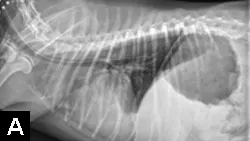

Tubes can be accidentally misplaced in the trachea (Figure 2A), nasopharynx, or nasal cavity, and subsequent feeding may result in aspiration pneumonia; therefore, appropriate placement should be confirmed before feeding is initiated. Various inexpensive methods can help verify tube location: laryngoscopic visualization of the tube entering the esophagus; suction to verify negative pressure; air infusion while auscultating the abdomen for borborygmus; infusion of sterile saline or nonionic contrast medium (Figure 2B), which sometimes elicits a cough with tracheal placement; or pH assessment of fluid aspirated from the tube.

Inadvertent placement of an NG tube in the trachea and bronchus of a miniature dachshund (11 years of age). This dog had a severe pulmonary interstitial pattern secondary to infusion of 20 mL of sterile saline through the tube; it had no cough reflex during infusion (A). After injection of 3 mL of iohexol 240, positive contrast medium outlined the alveoli, particularly in the caudodorsal thorax, confirming tube misplacement (B). The following day, radiography confirmed that contrast medium and saline had been cleared from the lungs.